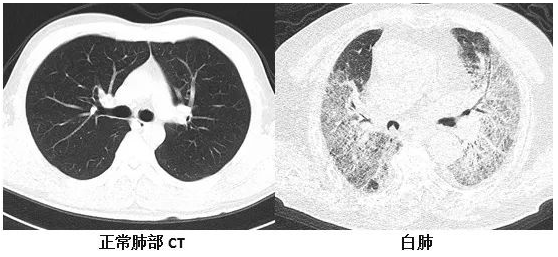

复旦大学附属华山医院感染科副主任医师张继明介绍,正常情况下,肺部主要是由充满了空气的肺泡组成,进行CT或者是X线检查时,射线可以很容易地穿透肺泡,在影像学上显示为黑色区域;当肺部受到病原体感染、临床上表现为重型肺炎时,患者肺泡里会出现炎症、渗出或实变时,射线不容易穿透病变区域,在影像学就出现了白色的区域。当白色区域面积达到了70%-80%时,临床上俗称其为“白肺”。事实上,“白肺”患者,其肺组织肉眼下看并不是白色的。

他表示,“白肺”是肺组织炎症渗出、肺实变所导致的一种影像学表现,“白肺”患者常常病情较为严重,预后较差。